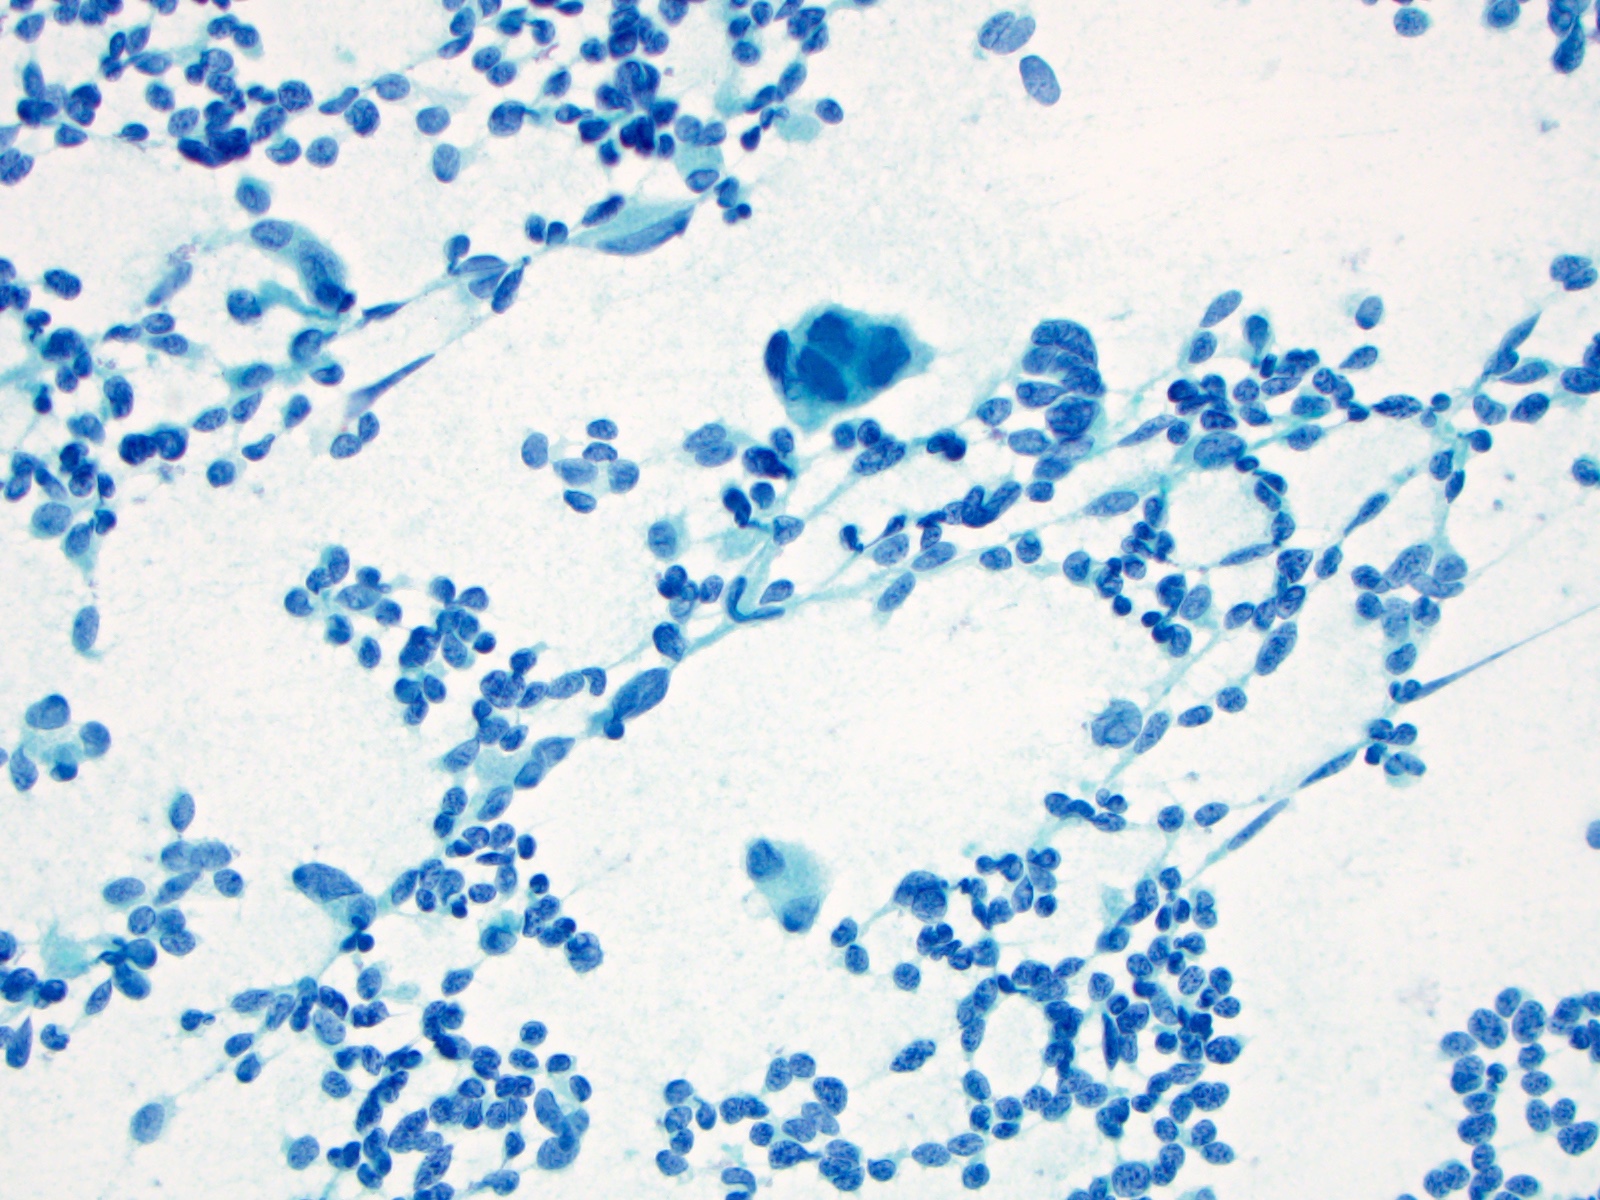

Cytology description

- Cellular specimen with round, ovoid, plasmacytoid or spindle cells singly or in small cluster; cells have abundant cytoplasm and eccentric nuclei; chromatin has salt and pepper appearance

- May have pink azurophilic granules and intranuclear pseudoinclusions; amyloid present occasionally (Am J Clin Pathol 1984;82:552)

- Paraganglioma-like variant:

- Predominantly ovoid to spindled epithelial cells in cohesive three dimensional clusters with sharp margins, rare isolated individual cells, no background colloid or amyloid

- Tumor cells have inconspicuous cytoplasm, significant nuclear atypia with occasional bizarre or binucleated cells, coarse and granular nuclear chromatin with occasional grooves and intranuclear inclusions (Cytopathology 2009;20:188)

Cytology images

Contributed by Ayana Suzuki, C.T. and Shuanzeng Wei, M.D., Ph.D.